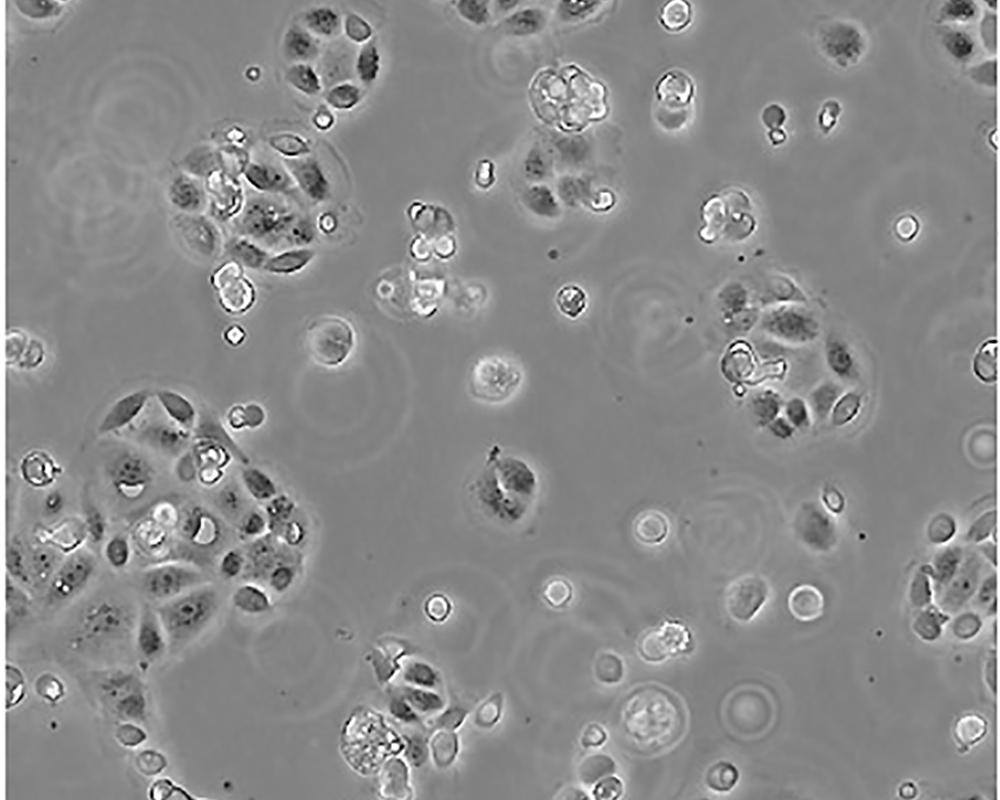

SW 1990

產(chǎn)品名稱 SW 1990

中文名稱 人胰腺癌細胞

形態(tài)特征 epithelial

細胞描述 1978年從胰腺外分泌腺的胰腺腺癌II期患者的脾轉(zhuǎn)移灶中建立了SW 1990細胞株。 報道該細胞的植板率為29%。